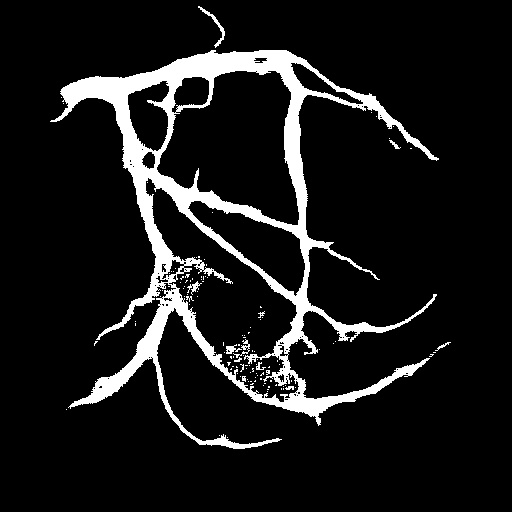

| Image | Ground truth | Video frame | Ground truth | Video frame | Ground truth |

| XCAD [33] | CADICA [19] | Our XACV dataset | |||

4.1 XACV Dataset

We collect 111 complete records of coronary artery X-ray videos, encompassing the injection, flow through the blood vessels around the heart, and dissipation of the contrast agent. Subsequently, we establish the XACV (X-ray Angiography Coronary Video) dataset. Each video consists of varying numbers of high-resolution coronary artery X-ray images. We invite experienced radiologists to annotate the vascular regions, focusing on one or two frames where the contrast agent is most prominent in each video. The XCAD dataset contains only a single image, and the CADICA video dataset does not provide corresponding ground truth. Therefore, in the following experiments, we conduct all the analyses on our collected XACV dataset and the corresponding GT for each sequence. In Figure 5, we show that compared to other publicly available datasets, XCAD [33] and CADICA [19], our dataset exhibits finer annotations in the vascular regions, providing an advantage for future related tasks. The development and use of our dataset have been approved by our institution’s IRB.